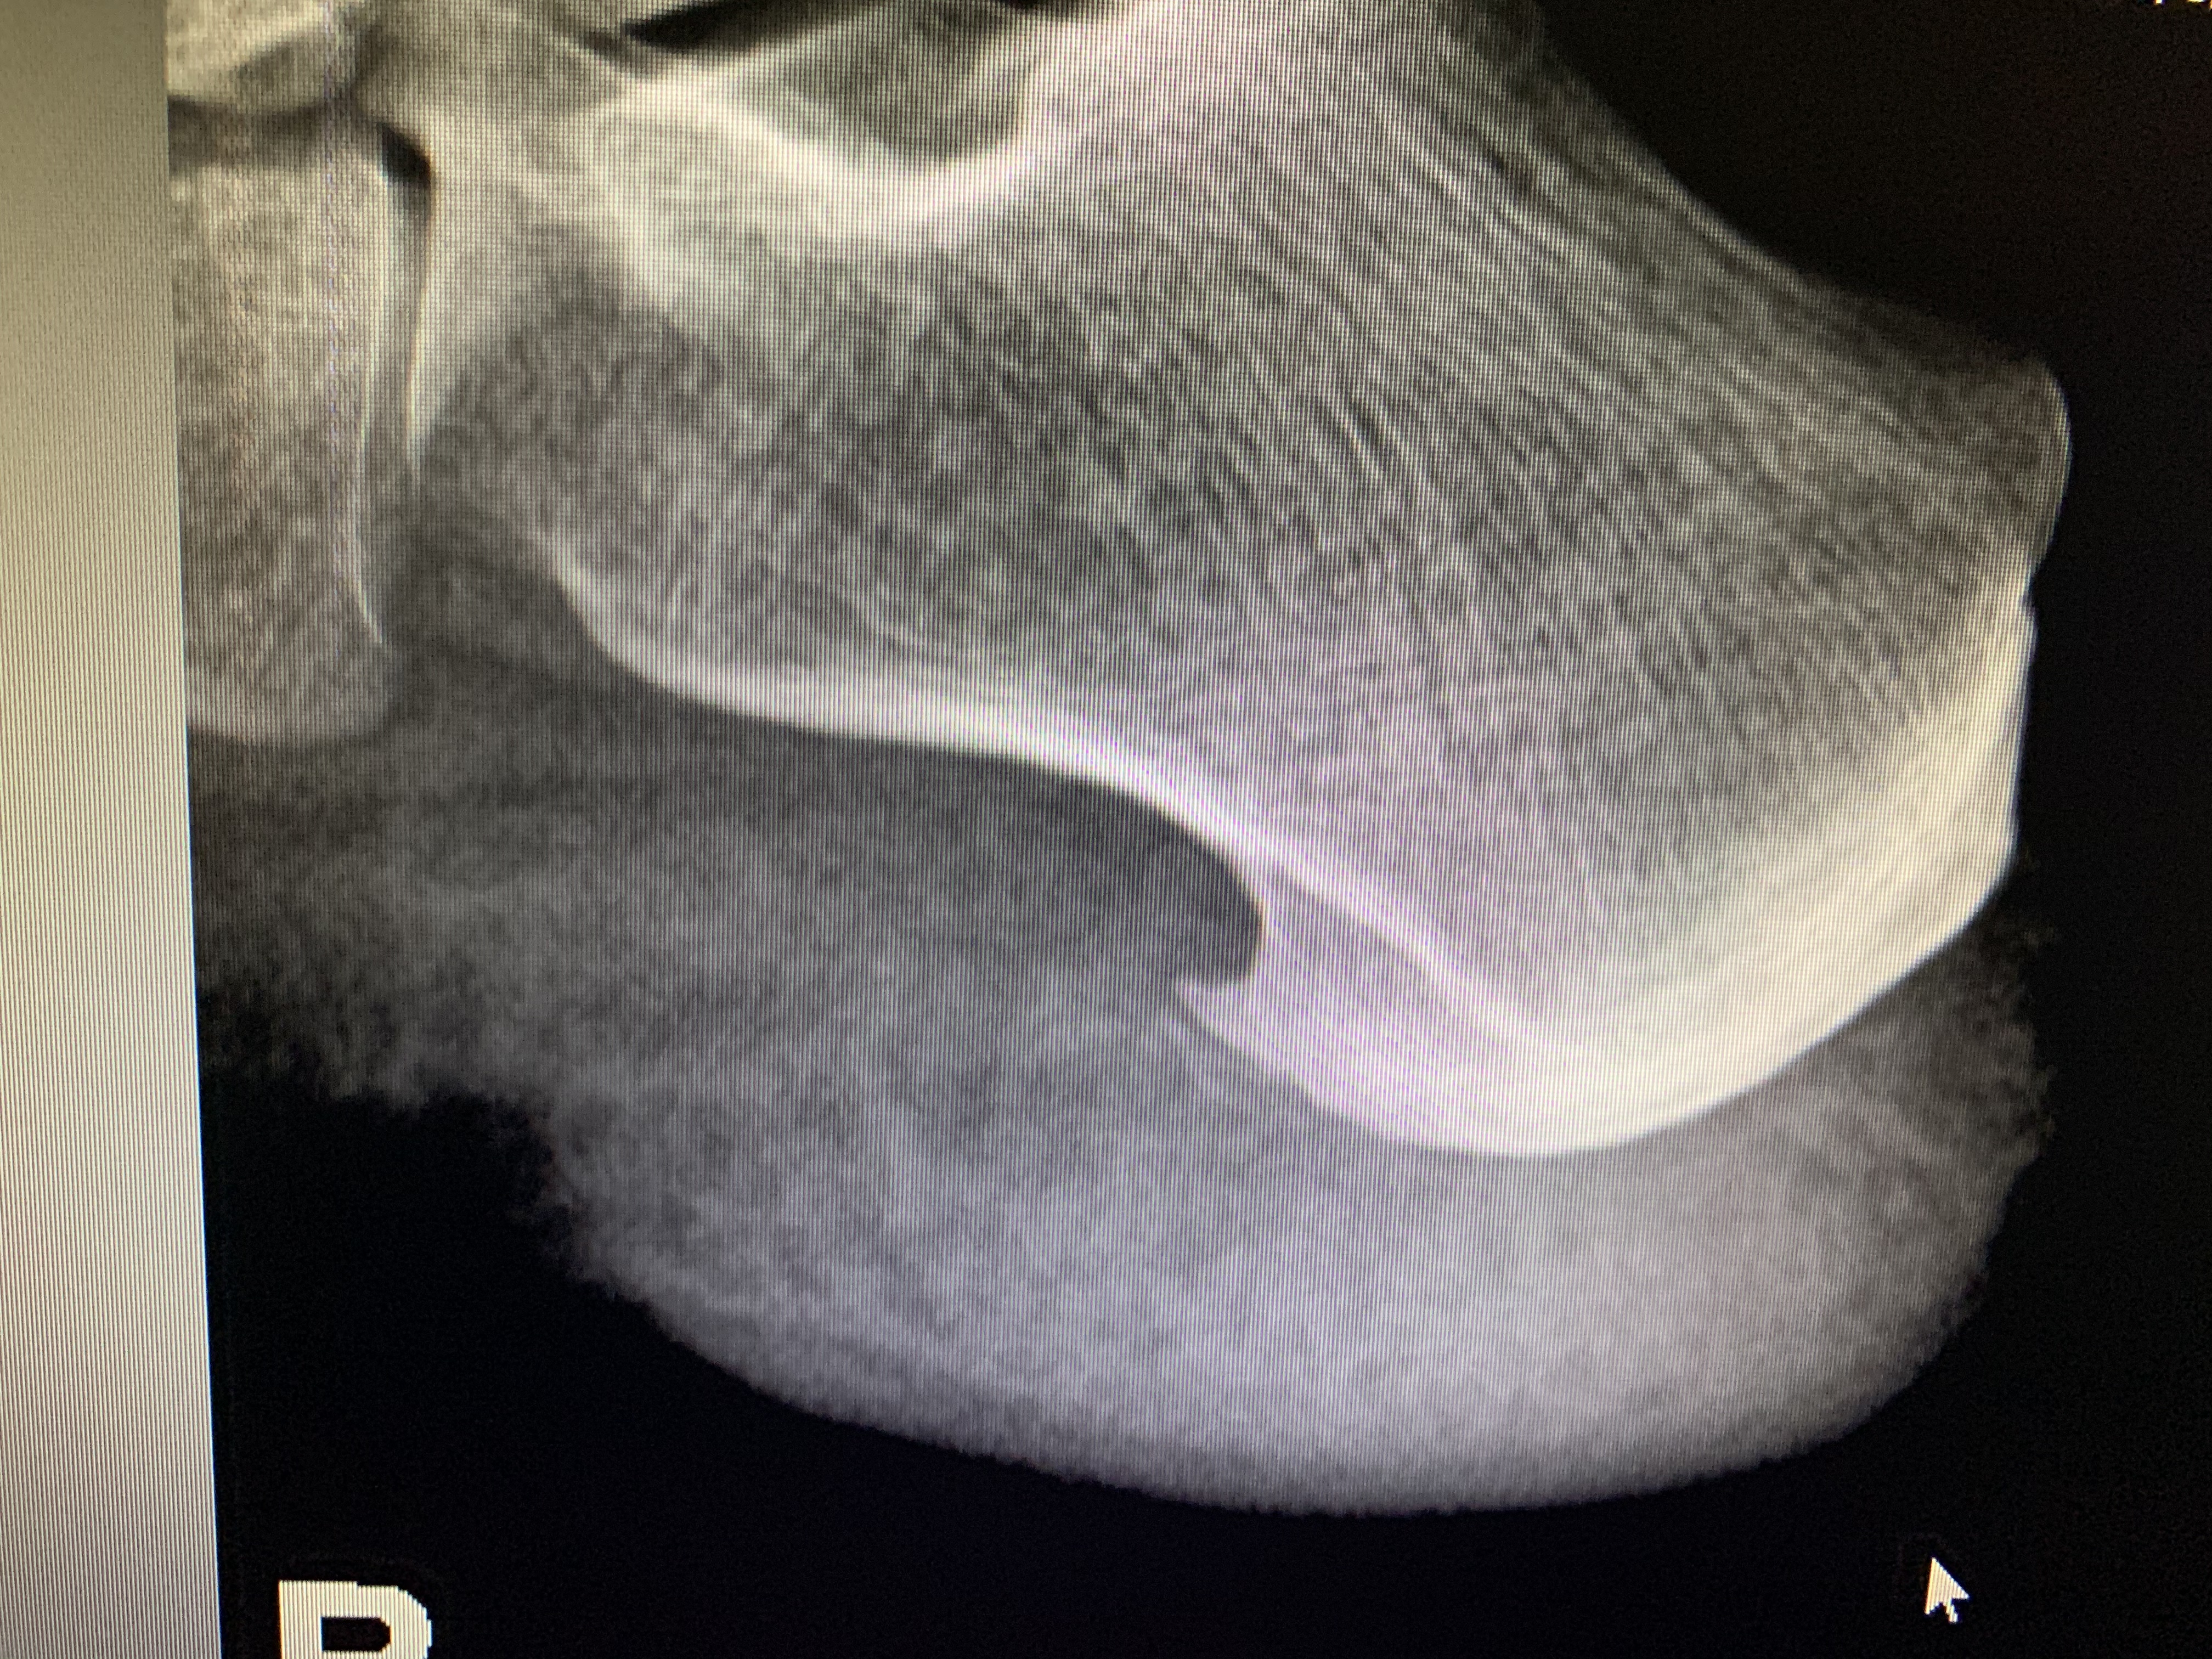

Galería de fotos clínica, servicios, cirugías, casos de pacientes Visítenos, ambiente limpio, agradable y seguro. Trabajando Operando en tiempos de coronavirus Dr Barquero Traumatologo Compartir en X (Se abre en una ventana nueva) X Comparte en Facebook (Se abre en una ventana nueva) Facebook Imprimir (Se abre en una ventana nueva) Imprimir Compartir en WhatsApp (Se abre en una ventana nueva) WhatsApp Enviar un enlace a un amigo por correo electrónico (Se abre en una ventana nueva) Correo electrónico Me gusta Cargando...